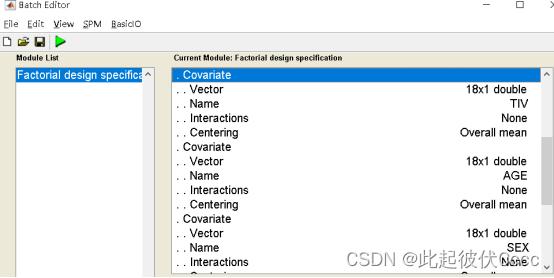

以TIV(之前在2.4步保存的文件)、年龄、性别作为协变量回归。(注意顺序)